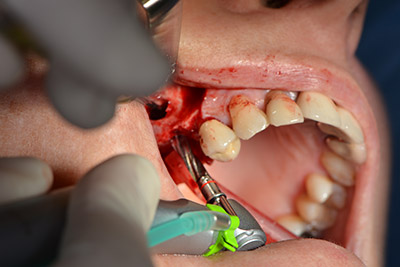

Die klassische Schnittführung (krestal, Entlastung bukkal) und das Präparieren des Mukoperiostlappens erlauben eine gute Übersicht.

In diesem Fall werden Sky Implantate (bredent) verwendet, deren chirurgisches Protokoll die Pilotbohrung mit etwa 1.200/min vorschreibt (Abb. 9).